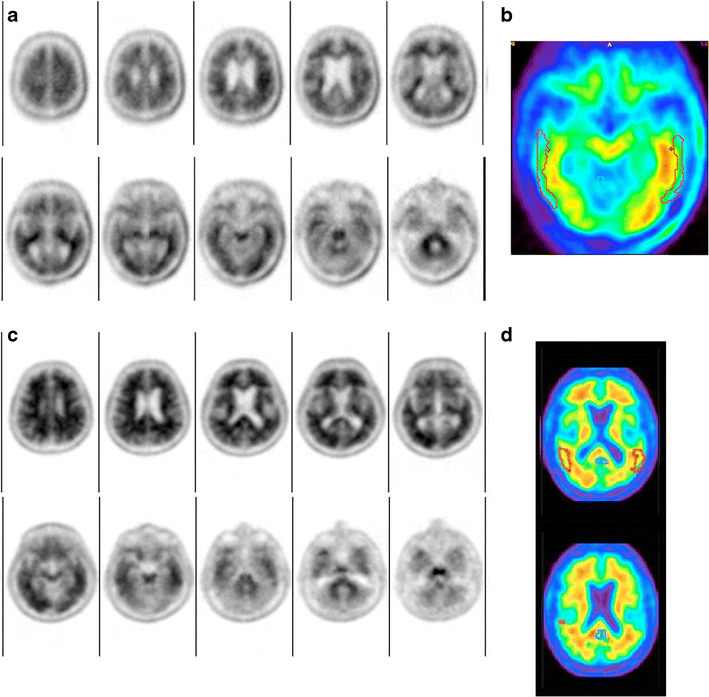

Florbetapir PET quantitation as an adjunct to visual read. a, b Florbetapir PET images from a subject diagnosed with Parkinson’s disease and confirmed to be Aβ− at autopsy. This scan was frequently interpreted by readers as positive (51 of 80) in the visual interpretation (day 1) but more than 50% of those incorrect interpretations were changed to negative (23 of 51) with quantitation as an adjunct. a Axial slices of a florbetapir PET scan from the top (upper left) to the bottom (lower right) of the brain in native space. b Slice from the same scan normalized to the template space using one of the commercial packages. Although the study did not record the thought processes of the readers, it is possible that they reviewed the quantitative result (normal SUVr) and the placement of the temporal lobe region of interest (red) and revisited their impression of whether the temporal cortex had loss of gray–white contrast. c, d Images from a 71-year-old man who was undergoing evaluation for mild cognitive impairment (no-autopsy group). Eight VisQ and one VisVis reader returned Aβ− interpretations on day 1. The quantitation result was positive (mean SUVr 1.39, with regional SUVr approximately 1.55 in both the precuneus and posterior cingulate), and all eight VisQ readers revised their interpretation to Aβ+. Possibly the readers reviewed the gray–white contrast in regions that overlapped the quantitative ROI and noticed the high level of signal in the precuneus/posterior cingulate regions (c top row, second and third slices)

Figure 2c, d shows images from another example patient, a 71-year-old man with a 15-month history of cognitive impairment and an Mini-Mental State Examination score of 25, who was undergoing evaluation for mild cognitive impairment of uncertain origin at the time of the florbetapir PET scan. The majority of readers in both the VisQ and VisVis cohorts interpreted this scan as Aβ+ on the initial visual read, but eight VisQ and one VisVis reader returned Aβ− interpretations on day 1. The quantitation result was positive (mean SUVr 1.39, with regional SUVr approximately 1.55 in both the precuneus and posterior cingulate), and all eight VisQ readers revised their interpretation to Aβ+, whereas the only change among the VisVis readers was an additional reader who recorded an Aβ− interpretation on day 2. According to the VisQ interpretation algorithm, after obtaining a positive quantitation result, readers should have checked the fit of the ROI to the PET scan (Fig. 2d), and then reviewed the gray–white contrast in regions that overlapped the quantitative ROI. In doing so might have noticed the high level of signal in the precuneus/posterior cingulate regions (Fig. 2c, top row, second and third slices). The positive quantitative values may also have reminded readers that the gray–white contrast in the cortex should be evaluated with respect to the presumed normal level of gray–white contrast seen in the cerebellum. In this case, even where the gray matter signal did not exceed that of the white matter (e.g., temporal lobe) the gray–white contrast was reduced relative to the cerebellum.